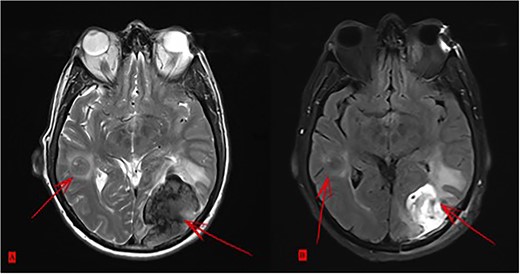

Postoperatively, tumor marker levels stabilized and a new chemotherapy regime with capecitabine (Xeloda) and gemcitabine (Gemzar) were started. Nonetheless, 40 months after first presenting, the patient developed two brain metastases following an 8-week break from chemotherapy. The larger lesion was surgically resected and the smaller was treated with gamma knife. Histology was consistent with metastatic PDAC (Fig. 5). Unfortunately, the patient died 42 months after first presenting, suffering multiorgan failure. Overall, the patient survived at least 40 months after multimodal therapy with good quality of life, despite the extensive synchronic LMs and the devastating diagnosis.

(A) Two brain metastases. (B) Status after surgical intervention on the bigger lesion.